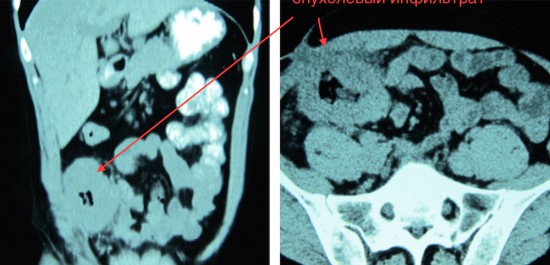

Рецидив рака слепой кишки